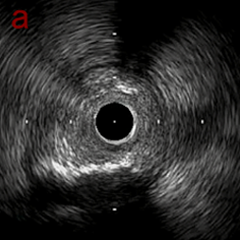

IVUS imaging

IVUSでは8時方向からPD枝がはいいてくる。

PreのIVUSではaの部位のみlipid plaqueを認め削ることでdistal embolismのリスクがあり、そのほかは270度の偏心性石灰化であるがwire biasは良好。